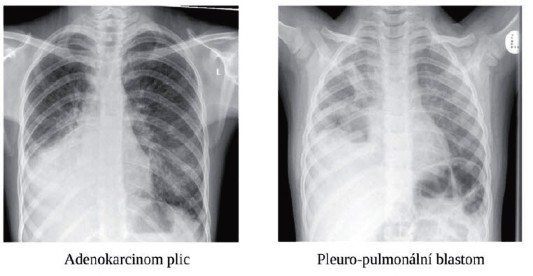

Pro malé děti je typickým primárním maligním nádorem plic pleuropulmonální blastom.

U dospívajících je nejčastějším primárním epiteliálním nádorem plic a bronchů karcinoid (dobře diferencovaný neuroendokrinní nádor). Obvykle je lokalizován v oblasti hlavních bronchů. Ve stejné lokalizaci se může vyskytnout i mukoepidermoidní karcinom, který je u mladých lidí většinou nízkého stupně malignity. Adenokarcinom je u mladé generace histologicky podobný konvenčnímu nemalobuněčnému adenokarcinomu plic v starším věku a chová se mimořádně agresivně. Zvláštní variantou adenokarcinomu plic u mladších dětí je dobře diferencovaný fetální adenokarcinom s dobrou prognózou. U dospívajících se tato forma nevyskytuje.

Primární maligní nádory plic byly diagnostikovány u 3 pacientek – 2 dívky v útlém věku měly diagnostikován typický embryonální nádor plic – extrémně vzácný pleuro-pulmonální blastom, v současnosti jsou na aktivní onkologické léčbě. U1 dívky byl diagnostikován špatně diferencovaný nemalobuněčný adenokarcinom plic ve věku 16 let (obr. č. 4). Kromě postižení plic bylo přítomno i postižení pleury a přítomna masivní diseminace nemoci s mnohočetnými kostními metastázami, metastázami do mozku, sítnice, ledvin a paraoartálních LU. I přes intenzivní léčbu 1. a 2. linie včetně biologické léčby dívka umírá na progresi nádoru 9 měsíců od diagnózy.